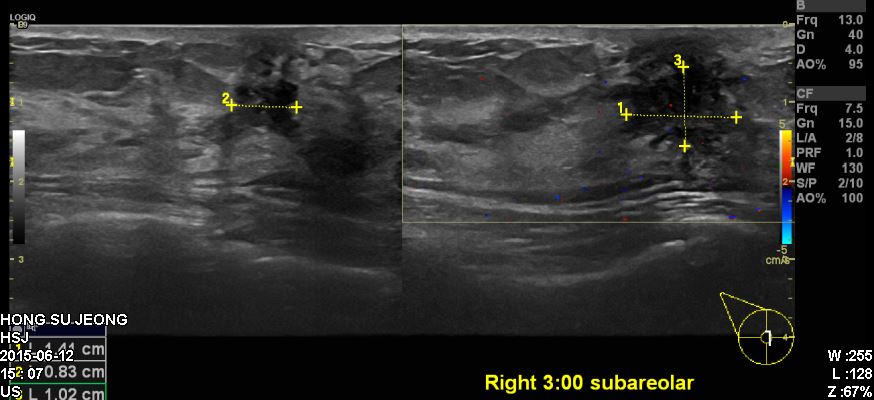

우측유방에 겨드랑이에 통증으로 내원하신 30대 환자분이십니다.

본원에서 유방초음파 시행 후 우측 3시방향에 확인되는혹 조직검사시행하였고

결과상 침윤성 유관암진단되었습니다.